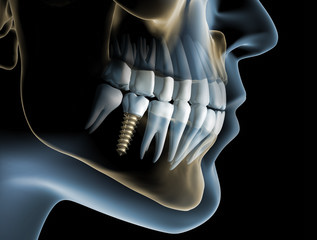

Implantologie

Durch eine sorgfältige Planung und moderne Diagnostik erzielen wir ästhetisch und funktionell überzeugende Ergebnisse.